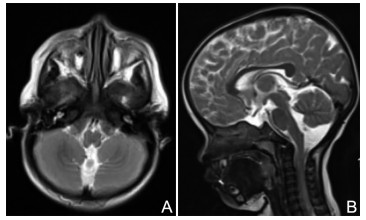

神经超声联合神经磁共振成像在吉兰-巴雷综合征诊断中的意义及机制研究

时鹏, 武心语, 怀玉水, 宋宏伟, 年娣

2025, 23(8): 1292-1297. doi: 10.16766/j.cnki.issn.1674-4152.004118

摘要:

目的  探讨神经超声联合神经磁共振成像在吉兰-巴雷综合征(GBS)患者诊断中的作用及机制。  方法  选取蚌埠医科大学第一附属医院2021年10月—2025年2月被诊断为GBS的患者43例,另选取24例健康体检者作为对照组。依据临床症状、体征及神经电生理检查将患者分为急性炎性脱髓鞘性多发神经根神经病(AIDP)和急性运动轴突性神经病(AMAN)两个亚型组,采用神经超声测量颈神经根、肢体周围神经横断面积(CSA);神经磁共振成像测量颈神经根、腰骶神经根CSA;吉兰-巴雷综合征残疾评分量表(GDSS)评估GBS患者神经功能缺失程度,分析CSA与神经缺损程度之间的相关性;收集外周静脉血,ELISA试剂盒测定外周血中细胞焦亡炎性因子水平。  结果  与对照组相比,AIDP组和AMAN组神经根、肢体周围神经增粗,CSA升高,其中神经超声示3组C5、C6比较差异均有统计学意义(H=20.216,P < 0.001;H=12.452,P=0.002);磁共振成像结果显示,与AMAN组和健康对照组相比, AIDP组患者C4~C8、L3~S1的CSA显著升高,差异均有统计学意义(P < 0.01);周围神经CSA与神经功能缺损程度呈正相关关系(P < 0.05);GBS患者外周血焦亡炎性因子水平较对照组升高,差异有统计学意义(P < 0.05)。  结论  GBS患者神经根和周围神经CSA值升高和神经功能缺损可能与焦亡途径激活导致的炎症级联反应有关,联合神经影像学和炎性因子检测有助于GBS的早期诊断,为GBS诊疗提供新思路。